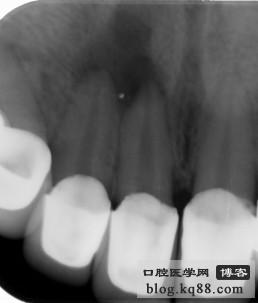

左下5側(cè)支根管被根充